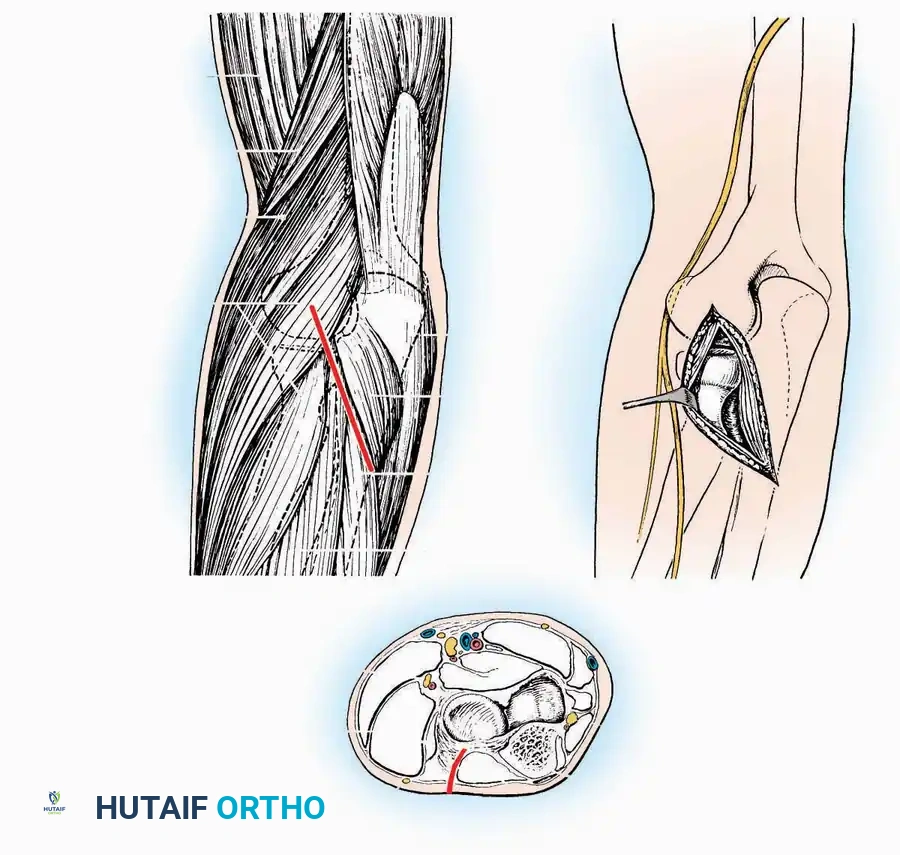

* Incision: Begin 2.5 cm anterior and 4 cm inferior to the medial malleolus. Carry it posteriorly along the medial surface of the foot toward the Achilles tendon.

* Superficial Dissection: Divide the fat and fascia to define the inferior margin of the abductor hallucis muscle.

* Deep Dissection: Mobilize the abductor hallucis muscle belly and retract it dorsally to expose the medial and inferomedial aspects of the calcaneal body.

* Plantar Exposure: Continue distally by dividing the plantar aponeurosis and the muscular attachments to the calcaneus, or strip them subperiosteally with an osteotome.

* Neurovascular Warning: Meticulously identify and protect the medial calcaneal nerve and the nerve to the abductor digiti minimi (first branch of the lateral plantar nerve), which are highly vulnerable during inferior retraction.